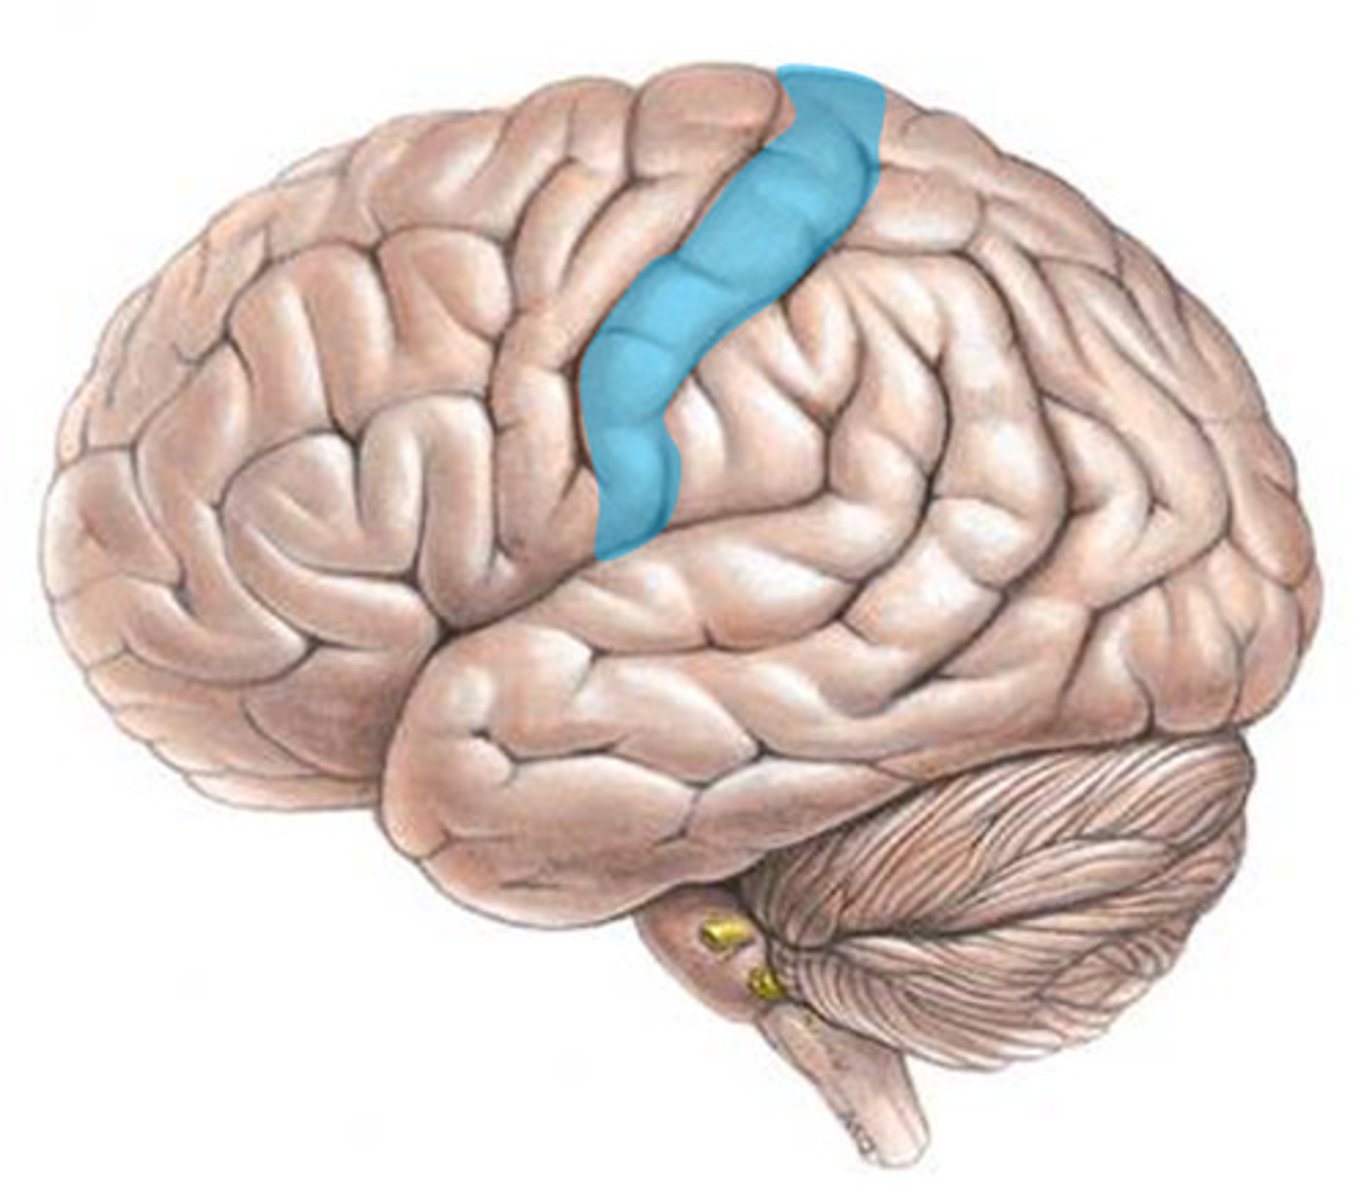

Precentral cerebral gyrus

primary motor cortex of the cerebrum is situated anterior to the central sulcus

postcentral gyrus

the strip of parietal cortex, just behind the central sulcus, that receives somatosensory information from the entire body

primary motor cortex

located in the frontal lobe; is the key motor control center responsible for initiating and coordinating movements